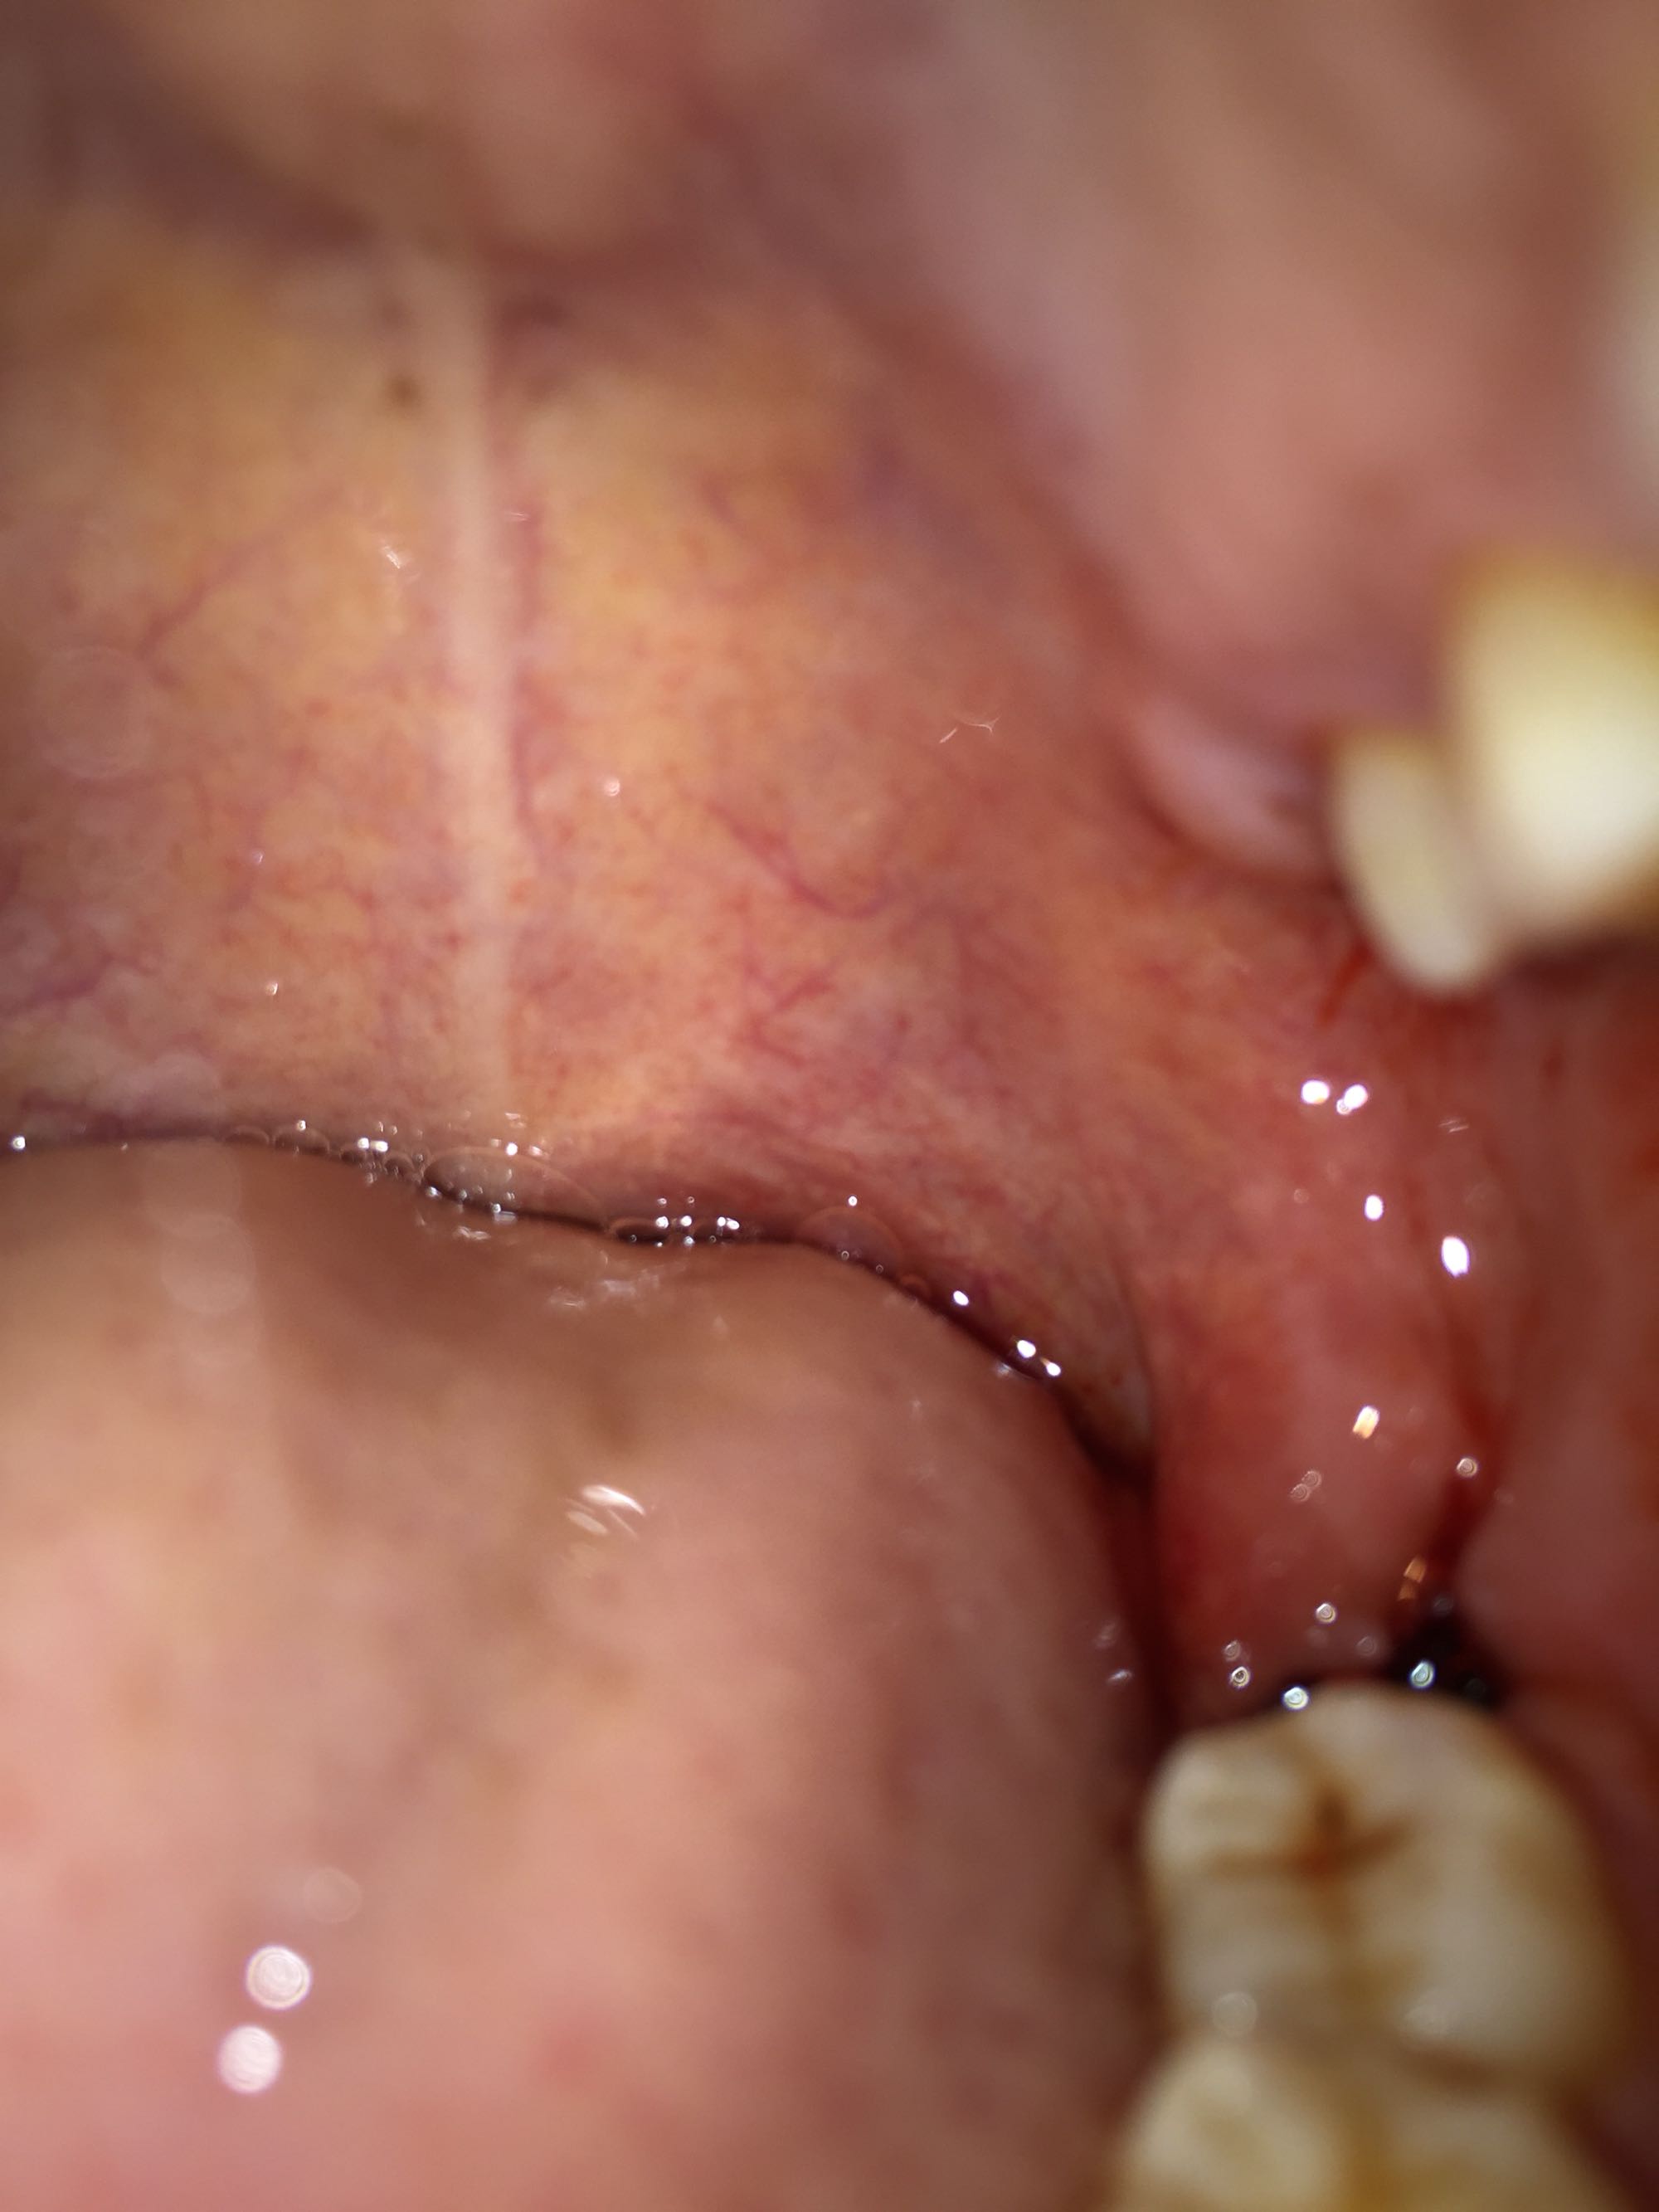

现在感觉拔牙创口那里不是很疼,但是淋巴开始肿了,又肿又疼,可难受了……说是两小时后可以进食,可是我宁愿饿着……![[暗中观察]](/static/emoticons/u6697u4e2du89c2u5bdf.png)

现在感觉拔牙创口那里不是很疼,但是淋巴开始肿了,又肿又疼,可难受了……说是两小时后可以进食,可是我宁愿饿着……